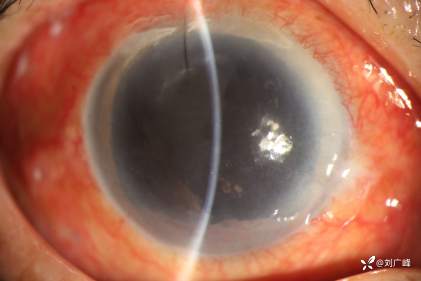

眼外伤术后硅油眼高眼压1例(瞳孔缝合+内路光凝)

男性 50+ 既往高度近视,眼外伤视网膜脱离、脉络膜脱离,其他医师做的玻切术,硅油眼,眼压40-50mmHg 2周,应用降眼压药物治疗。

角膜水肿,瞳孔散大至周边,周边虹膜与角膜相贴敷。